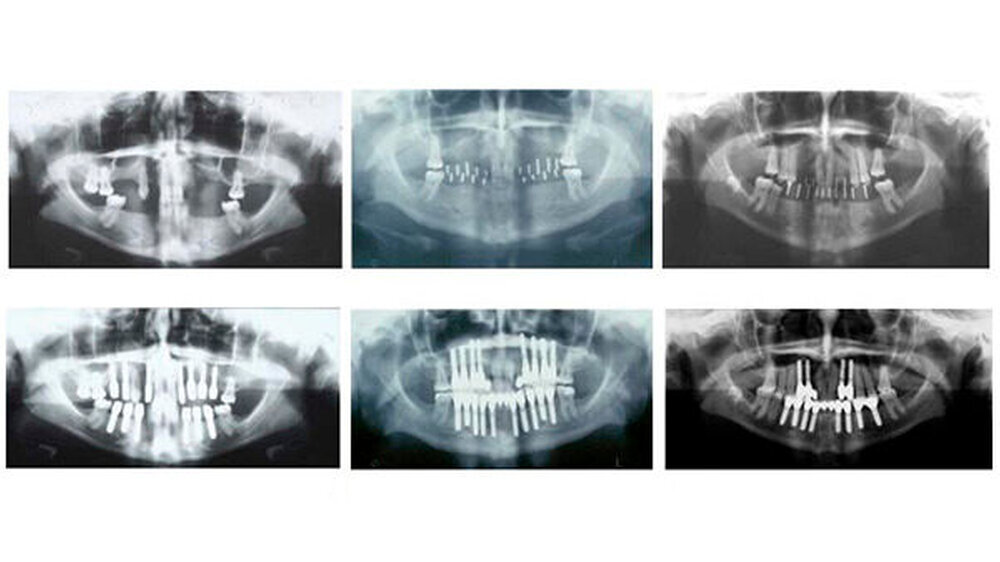

Die definitive Prothetik wurde vier Monate später eingesetzt. Seither erfolgen regelmäßige Verlaufskontrollen und wichtige Hygienemaßnahmen. Auf den aktuellen Panoramaschichtaufnahmen, die bis zu 14 Jahre nach Abschluss der Behandlung erfolgten, stellt sich ein stabiles periimplantäres Knochenniveau bei allen drei Patientinnen dar. Die klinischen Untersuchungsparameter an sämtlichen Implantaten waren unauffällig. Sowohl in der Funktion als auch in der Ästhetik ist ein Langzeiterfolg zu verzeichnen.